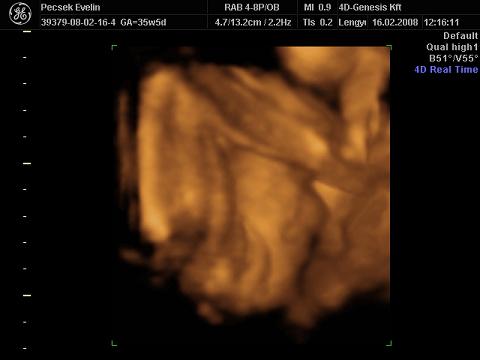

Liza megmutatta az arcát a végére (egész végig takarta a kezével és lábával, bezzeg a punciját azt nem):

Kép

Voltunk a dokinál 12-én, zárt a méhszáj, fejvégü Liza, viszont a vizeletembe genny volt, ezért írt fel antibiotikumot (Xorimax-ot), azt kellett szednem 5 napig napi 2x. Azt mondta, hogy nem kell aggódni, ez a terhesség vége felé elő szokott fordulni, ha nem iszok megfelelő mennyíségű folyadékot, mert a vesém már nagyon meg van így is terhelve. Rám viszont nagyon igaz, hogy keveset iszok, sajnos nem megy, nem kívánom :oops: :cry: Majd most pénzteken (29-én) kell visszamenni a dokibácsihoz, kiváncsi leszek mit mond. Most kezdi el a CTG-t.

Viszont mindenki azt mondja a környezetembe (a családba is és ha vásárolni megyek akkor az eladók is), hogy nagyon lent van a hasam. A 4D Genesis-es nőci is azt mondta miközben csinálta az UH-t, hogy nagyon lent van a lepény és a baba feje is, a lepény 2-es fokban érett :shock: :shock: Lehet, hogy hülye kérdés, de ez most mit jelent?